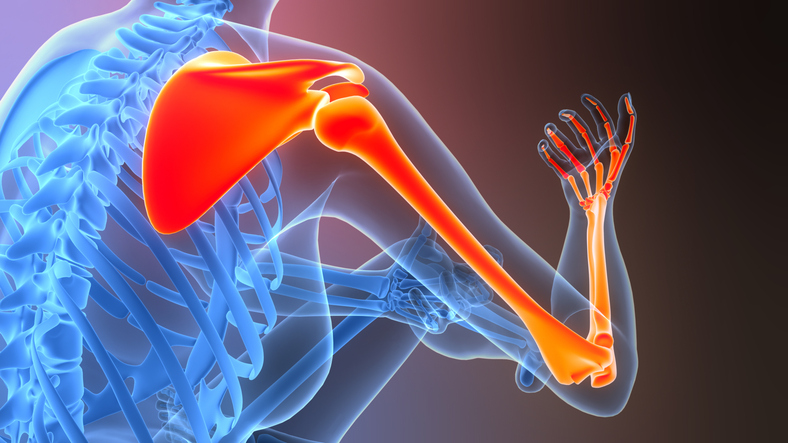

- Shoulder Arthroplasty: Advancing prosthesis durability and post-operative function through research